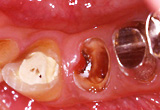

- Case1 残根(大きなむし歯)や破折歯の治療。

- 歯根を引っ張り出して治療します。